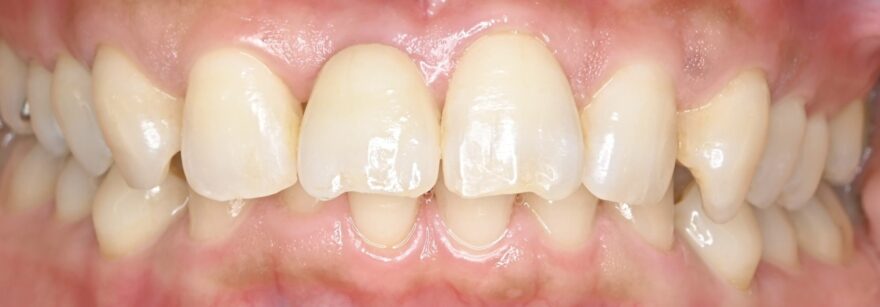

初診時口腔内写真

左側の差し歯が壊れてしまい、当院を受診されました。

治療後の口腔内写真とレントゲン写真